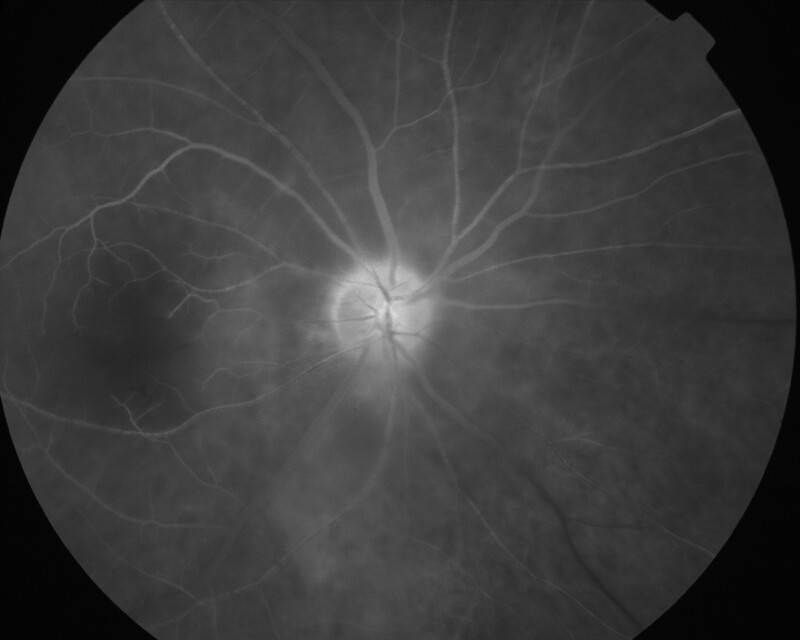

2002092401\24-09-2002

IMG0024.jpg